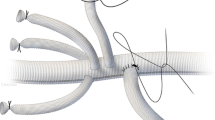

To understand the anatomy of the spinal cord vasculature and its physiological mechanisms as a reaction to critical changes in spinal cord perfusion is a vital first step toward improved treatment. The spinal cord is nourished by three major arteries: the anterior spinal artery (ASA ) feeds the anterior two-thirds of the spinal cord, and two posterior spinal arteries provide blood flow to the posterior third. Arising from the aorta, intercostal and lumbar arteries give off branches to the spinal arteries: the anterior and posterior radicular–medullary arteries (ARMA, Fig. 7.1).

High-resolution CT scan of the vasculature. The aorta (1) gives rise to the segmental arteries (2), which run around the vertebral bodies and connect to the anterior spinal artery (3) through the anterior radicular–medullary arteries (4), and give off branches to the epidural arcades (5). Its connections with the dense vasculature within the paraspinous muscles can also be seen (6). Reprinted from The Journal of Thoracic and Cardiovascular Surgery, 144(6), Geisbusch S, Schray D, Bischoff S, Lin HM, Griepp RB, Di Luozzo G, Imaging of vascular remodeling after simulated thoracoabdominal aneurysm repair, 1471–8, Copyright 2012, with permission from Elsevier

There are multiple longitudinal interconnections between the blood supply of the muscles, an extensive epidural system, and the anterior spinal artery, with numerous anastomoses at every thoracic and lumbar level between these various components of the network. A reconstruction based on several casts of the paraspinal and intrathecal vessels is shown in Fig. 7.5 [9].